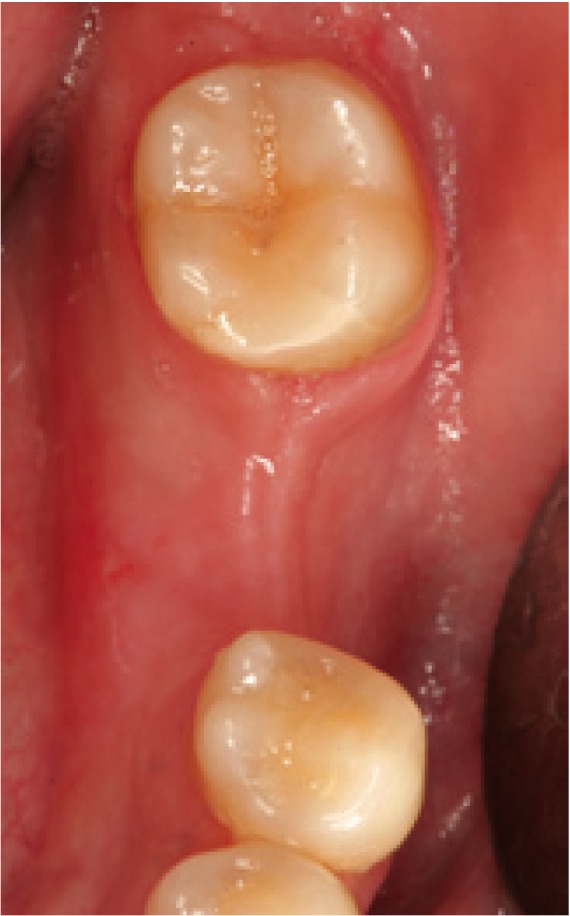

Figure 1.

Preoperative view. Note the insufficient attached mucosa for performing surgery with the circular scalpel.